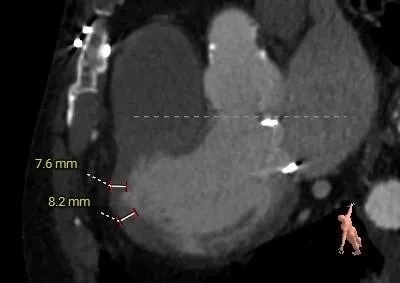

Case 3:单纯重度狭窄+左室心肌肥厚——分步释放保障瓣膜稳定性

瓣架内径:25mm

瓣架外径:28.5mm

心室侧2mm:24.6mm

心室侧4mm:24.6mm

心室侧6mm:24.3mm

心室侧8mm:23.3mm

心室侧10mm:22.6mm

心室侧12mm:22mm

瓣架高度:18mm

neo-LVOT:516.9mm²

左室心肌厚度:7.6mm

瓣环切线位:RAO60°,CRA20°

第五肋间切口,心尖轻度转位,过肋弓,靠近胸骨中线方向

预选瓣膜型号:ScienCrown TAVTF25mm。

选瓣依据:该二尖瓣原置换生物瓣型号未知,CT测量生物瓣瓣环周长折算直径约25.0mm,瓣架高度约18mm。

植入深度:心房侧1/5~1/4瓣架长度,约mark点平齐瓣环。